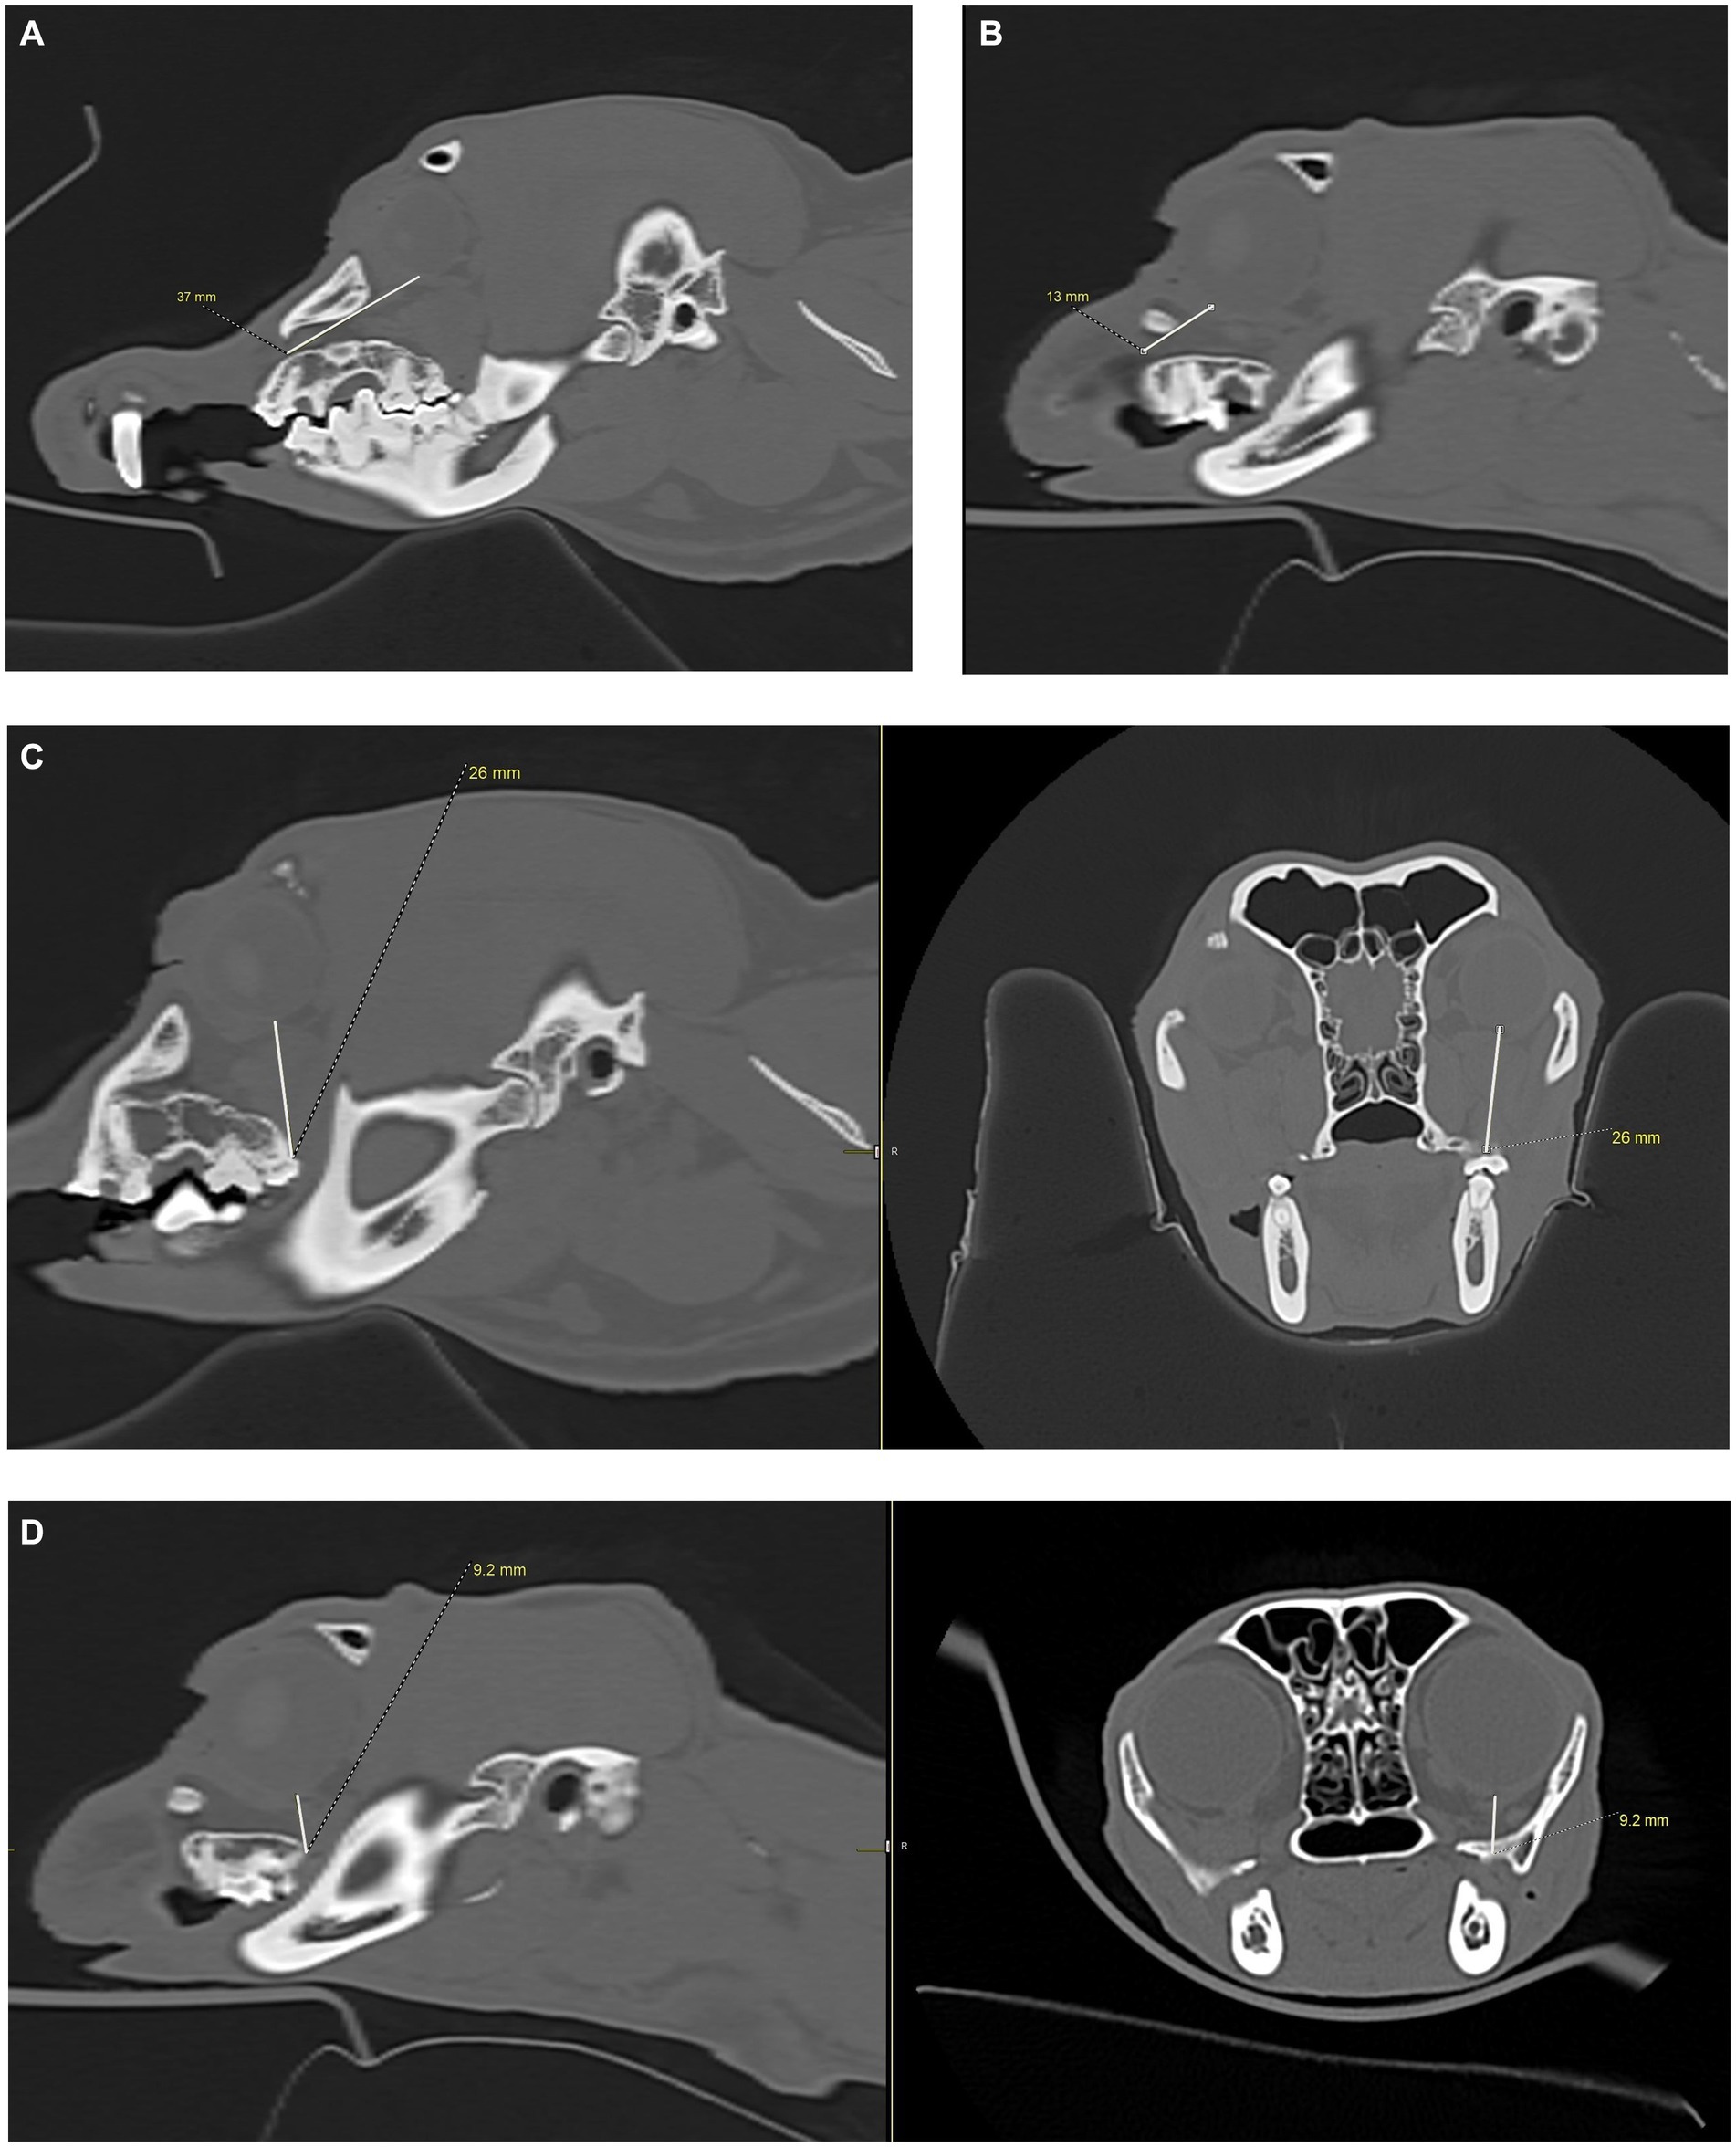

Figure 3

CT scans of the nasal region of a dog showing four different transverse views labeled A, B, C, and D. Images A and B contain arrows pointing to the infraorbital and maxillary foramina. Image C shows measurement of the infraorbital canal height and indicates a measurement of 9.4 millimeters, while image D shows measurement of the infraorbital canal width and shows a value of 3.6 millimeters.

Figure 3. Infraorbital canal length measurement, in millimeters, was taken using the CT transverse view, from the infraorbital foramen to the maxillary foramen in the cat and dog. (A) The white arrow shows the right infraorbital foramen in a dog skull. A complete bony circle is barely visible. (B) The white arrow shows the right maxillary foramen in a dog skull. A complete bony circle is visible. (C) Image showing the height measurement of a dog’s left infraorbital canal. The measurement was collected at the infraorbital foramen. (D) Image showing the width measurement of a dog’s left infraorbital canal. The measurement was collected at the infraorbital foramen.